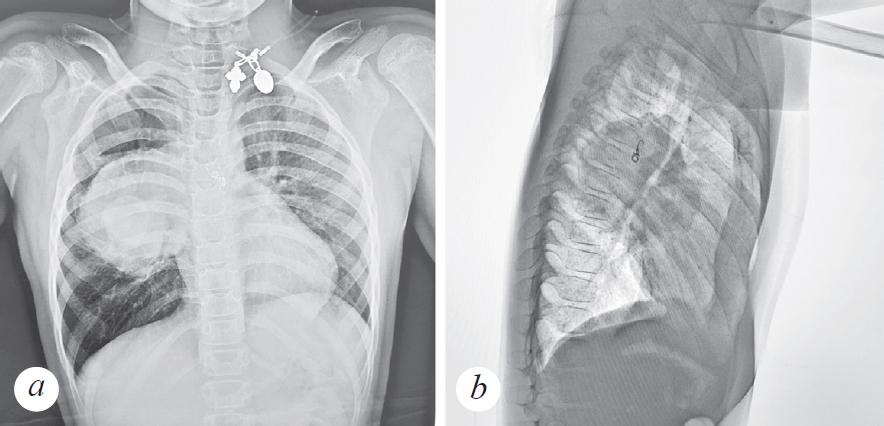

На момент госпитализации болен, со слов родителей, 10 дней. Начало заболевания — покашливание, умеренная астения. Осмотрен педиатром по месту жительства, состояние расценено как течение острой респираторной вирусной инфекции, назначена симптоматическая терапия Амброгексалом. На фоне лечения — без улучшения, отмечается повышение температуры до 38 °C, кашель, в связи с чем ребенка повторно осматривал участковый педиатр, коррекция терапии не проводится. Мама самостоятельно начала давать мальчику Амоксиклав. На 2-й день приема антибиотика, со слов родителей, отмечалось улучшение самочувствия, нормализация температуры тела, уменьшение кашля. Семья уехала на отдых в Карелию, где на 3-й день пребывания у ребенка наблюдается резкое ухудшение состояния в виде выраженной одышки, отказа от еды и питья, слабости. С данными жалобами ребенок госпитализирован в ГБУЗ РК «Сортавальская ЦРБ». Состояние при поступлении расценено как тяжелое. Мальчик вялый, адинамичный. При осмотре отмечается бледность кожных покровов, одышка смешанного характера до 40–46 дыханий в минуту, SpO2 90 %. Зев без катаральных явлений. Периферические лимфоузлы не увеличены. Носовое дыхание свободное. Аускультативно в легких: справа ослабленное дыхание, сухие свистящие хрипы по всем легочным полям. Перкуторно над легкими: укорочение легочного тона справа в проекции средней доли. Тоны сердца ясные, ритмичные, 102 в минуту. Артериальное давление 95/60 мм рт. ст. Живот мягкий, безболезненный, печень по краю реберной дуги, селезенка не пальпируется. Физиологические отправления в норме. В клиническом анализе крови при поступлении гемоглобин 119 г/л, эритроциты 4,48 · 1012/л, лейкоциты 6,68 · 109/л, тромбоциты 336 · 109/л, палочкоядерные нейтрофилы 5 %, сегментоядерные нейтрофилы 85 %, лимфоциты 6 %, моноциты 4 %. В биохимическом анализе крови: общий белок 66,7 г/л, С-реактивный белок 33,7 ед., аланинаминотрансфераза 14,7 U/I, аспартатаминотрансфераза 28,0 U/I, билирубин общий 5,3 ммоль/л, глюкоза 7,52 ммоль/л, мочевина 5,0 ммоль/л, креатинин 23 ммоль/л. Общий анализ мочи: лейкоциты 20–22 в поле зрения, эритроциты 25–27 в поле зрения. Коагулограмма: Д-димер 3,27. На рентгенограмме легких (прямая и правая боковая проекция, рис. 1) и СКТ легких (рис. 2) — справа, в проекции SVI, огромное образование с ровными и четкими контурами, плотной интенсивности, не сопровождающееся нарушением проходимости бронхов.

Рис. 1. Пациент, 8 лет. Прямая (a) и правая боковая рентгенограмма (b) грудной клетки — справа, в проекции S6, огромное образование с ровными и четкими контурами, плотной интенсивности, не сопровождающееся нарушением проходимости бронхов